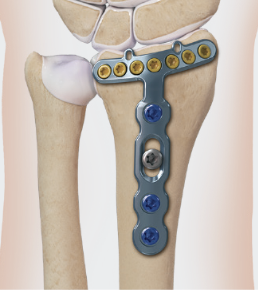

Fragment specific plates

| Volar locking plates | Volar rim plates | Radial styloid plates |

Supplementary radial column fixation |